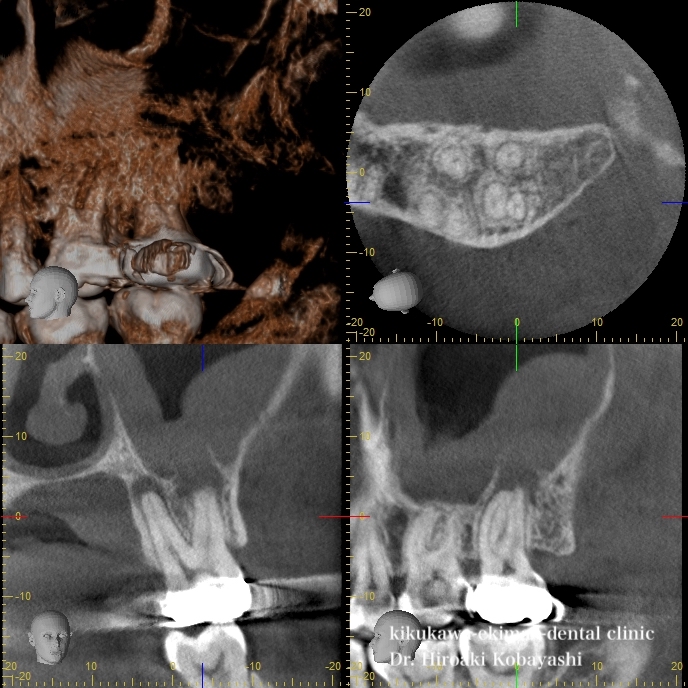

このCT画像は歯の神経が腐り細菌感染が起こった事により、上顎洞炎が起こり、顎の骨の吸収が起こっていました。このまま放置すると鼻から膿が出てきたり、骨がの吸収がさらに大きくなると抜歯になります。